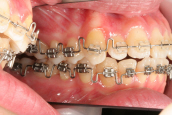

2015年4月2日から、矯正を開始しました。手術は行わず、原因である奥歯の高さの調整をして、同時に歯列の幅も広げました。ちょうど一年が経過しました。

2016年4月6日のお口です。歯は歯列におさまり、奥歯の噛み合わせも正常になっています。矯正治療は全ての歯を動かして並べ変える まさに「噛み合わせ治療」です。女性の平均寿命は85歳を越えています。これからの60年以上の時間 噛むことに耐えうる安定した状態を、歯を動かす矯正を利用して実現することを目標としています。

どの病気でも同じなのですが、診断が大切です。診断が違えば治療方法、結果が変わってしまいます。普通に生まれて普通に育ってきているのに、なぜ正常な噛み合わせに成長できなかったのでしょう。その原因は奥歯の萌出の高さにあります。その原因を調整することによって成人になっても正しい噛み合わせに移行できるのです。